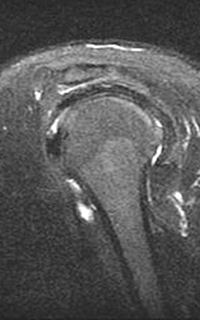

As some say, seeing is believing. Check out the images below which compares a low strength, open machine to a 1.5T, high-field machine. The difference in quality from one scan to another speaks for itself.

MRI of the Shoulder: High-field 1.5T MRI on the left; low-field, open on the right.